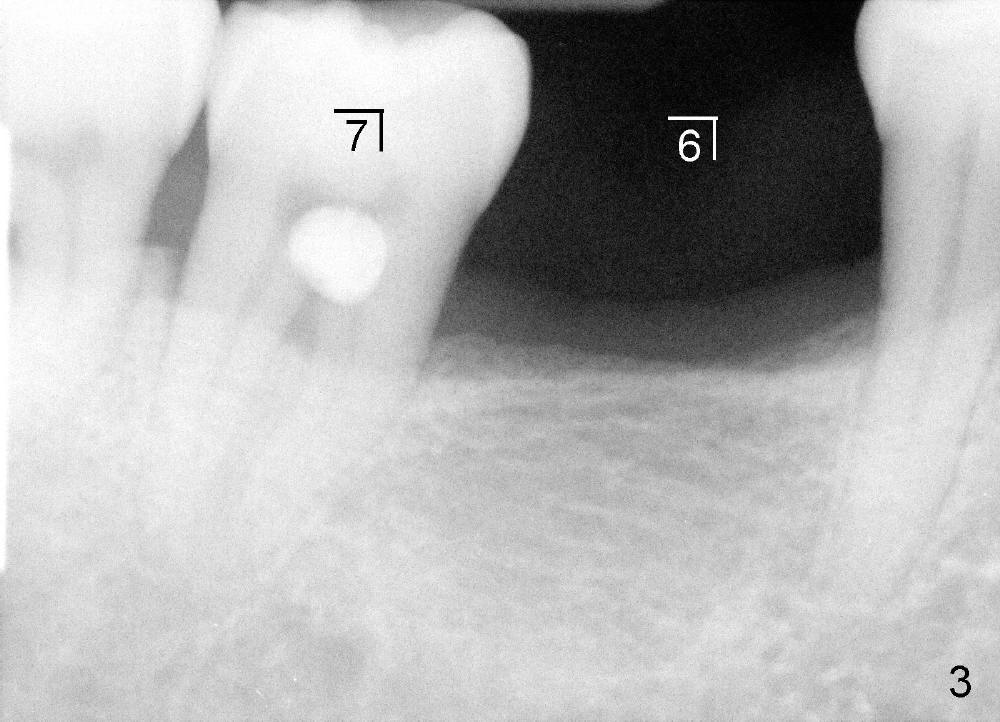

五十来岁郑先生有两个主诉:第一,左上桥松动(图二,五),要求拔除后面基牙;第二,右下六号牙处需要植牙(图三)。初步检查几张根尖片(图一至五),他是典型牙周病病人,悲观人认为不治之症,乐观人却认为这是最好植牙病例,虽然骨质吸收严重,但是剩下骨质坚硬,因为牙周病病人往往咬合力很大。充分利用剩余骨质吧。现在他口腔卫生不差。